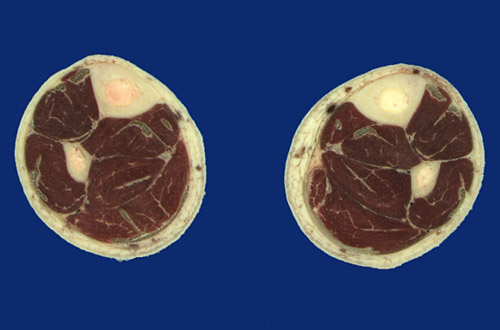

Identify the following regions in the image above: Tibia - Fibula - Posterior tibial artery & vein - Tibial nerve - Tibialis anterior tendon - Extensor hallucis longus - Interosseous membrane - Tibialis posterior - Flexor digitorum longus - Calcaneal tendon - Soleus - Flexor hallucis longus - Peroneus longus tendon - Peroneus brevis - Extensor digitorum longus